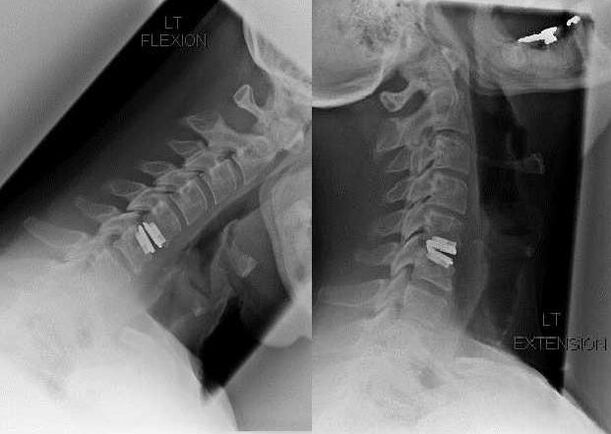

At the initial stage of development, osteochondrosis is asymptomatic.After a long stay with a bowed head or intense physical activity, mild discomfort occurs in the back of the neck.The patient is in no hurry to see a doctor, mistaking them for the consequences of muscle strain.The pathology is slowly but persistently progressing.

Discomfort in the neck is gradually replaced by aching, dull pain in the neck, intensifying after heavy lifting, hypothermia, or a change in weather.Other specific symptoms of cervical osteochondrosis appear:

- crunching, clicking when tilting or turning the head;

- limited mobility in the cervical spine;

- sharp, severe pain during exacerbations.

As the intervertebral discs and vertebrae deform, the patient's condition worsens.The course of osteochondrosis is complicated by neurogenic symptoms caused by compression by osteophytes or hernial protrusion of the spinal roots and vertebral artery.Headaches, dizziness, changes in blood pressure appear, and visual and hearing acuity decreases.